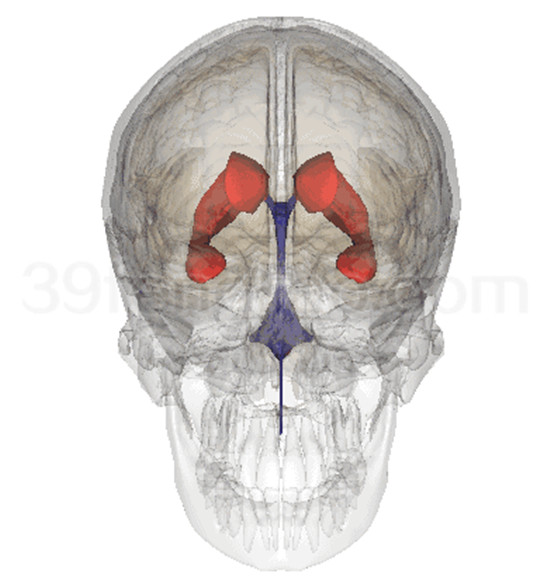

海马和穹窿